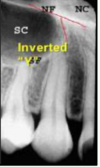

92

identify the anatomical structure below.

inverted "Y" - zygomatic process

intersection of maxillary sinus and nasal cavity

inverted "Y"